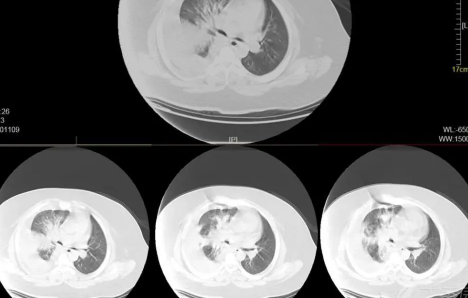

白肺是目前很常见的情况,受新冠影响很多老年人都出现了白肺的情况,当然也有年轻人会患上白肺。那么,如何自查是否出现白肺?平时怎样保护自己的肺?一起来看看趣丁网带来的详细介绍吧!

如果出现白肺,患者可能会出现一些严重的呼吸道症状,包括咳嗽、喘息、呼吸困难或体力活动时呼吸短促。一个更客观的指标是病人的呼吸频率,通常大于每分钟30次呼吸,或血氧饱和度低于93%就要警惕出现严重肺部感染。白肺并不能预防,只能预警。

肺白了还能恢复吗

肺白了一般是指白肺,白肺能否恢复与疾病类型、严重程度有一定关系,有些患者在检查时,发现肺白密度增高,如果是轻度肺部炎症引起的白肺一般是可以恢复的,如果是严重肺部炎症或肺间质纤维化引起的,则可能无法恢复。

如果是比较严重的肺炎或肺间质纤维化引起的白肺,一般会伴有呼吸困难的症状,首先应该改善患者的呼吸状态,可以帮助患者通过吸氧呼吸,也应该使用抗生素类药物进行治疗,症状消退后,白肺症状会相应减轻,但一般不会完全恢复。

此外,白肺也可能由肺结核、肺肿瘤等原因引起,需要鉴别诊断。